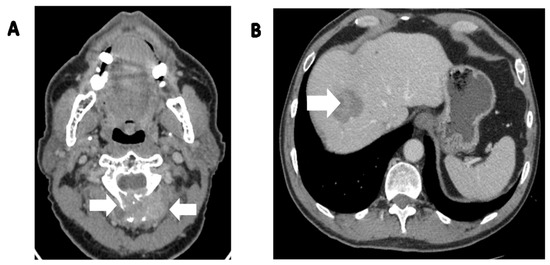

- Zhang, W.D.; Chen, J.Y.; Cao, Y.; Liu, Q.Y.; Luo, R.G. Computed tomography and magnetic resonance imaging findings of solitary fibrous tumors in the pelvis: Correlation with histopathological findings. Eur. J. Radiol. 2011, 78, 65–70. [Google Scholar] [CrossRef]

- Li, X.M.; Reng, J.; Zhou, P.; Cao, Y.; Cheng, Z.Z.; Xiao, Y.; Xu, G.H. Solitary fibrous tumors in abdomen and pelvis: Imaging characteristics and radiologic-pathologic correlation. World J. Gastroenterol. 2014, 20, 5066–5073. [Google Scholar] [CrossRef] [PubMed]

- Shanbhogue, A.K.; Prasad, S.R.; Takahashi, N.; Vikram, R.; Zaheer, A.; Sandrasegaran, K. Somatic and visceral solitary fibrous tumors in the abdomen and pelvis: Cross-sectional imaging spectrum. Radiographics 2011, 31, 393–408. [Google Scholar] [CrossRef] [PubMed]

- Liu, Y.; Tao, X.; Shi, H.; Li, K. MRI findings of solitary fibrous tumours in the head and neck region. Dentomaxillofac. Radiol. 2014, 43, 20130415. [Google Scholar] [CrossRef] [PubMed]

- Keraliya, A.R.; Tirumani, S.H.; Shinagare, A.B.; Zaheer, A.; Ramaiya, N.H. Solitary Fibrous Tumors: 2016 Imaging Update. Radiol. Clin. N. Am. 2016, 54, 565–579. [Google Scholar] [CrossRef] [PubMed]